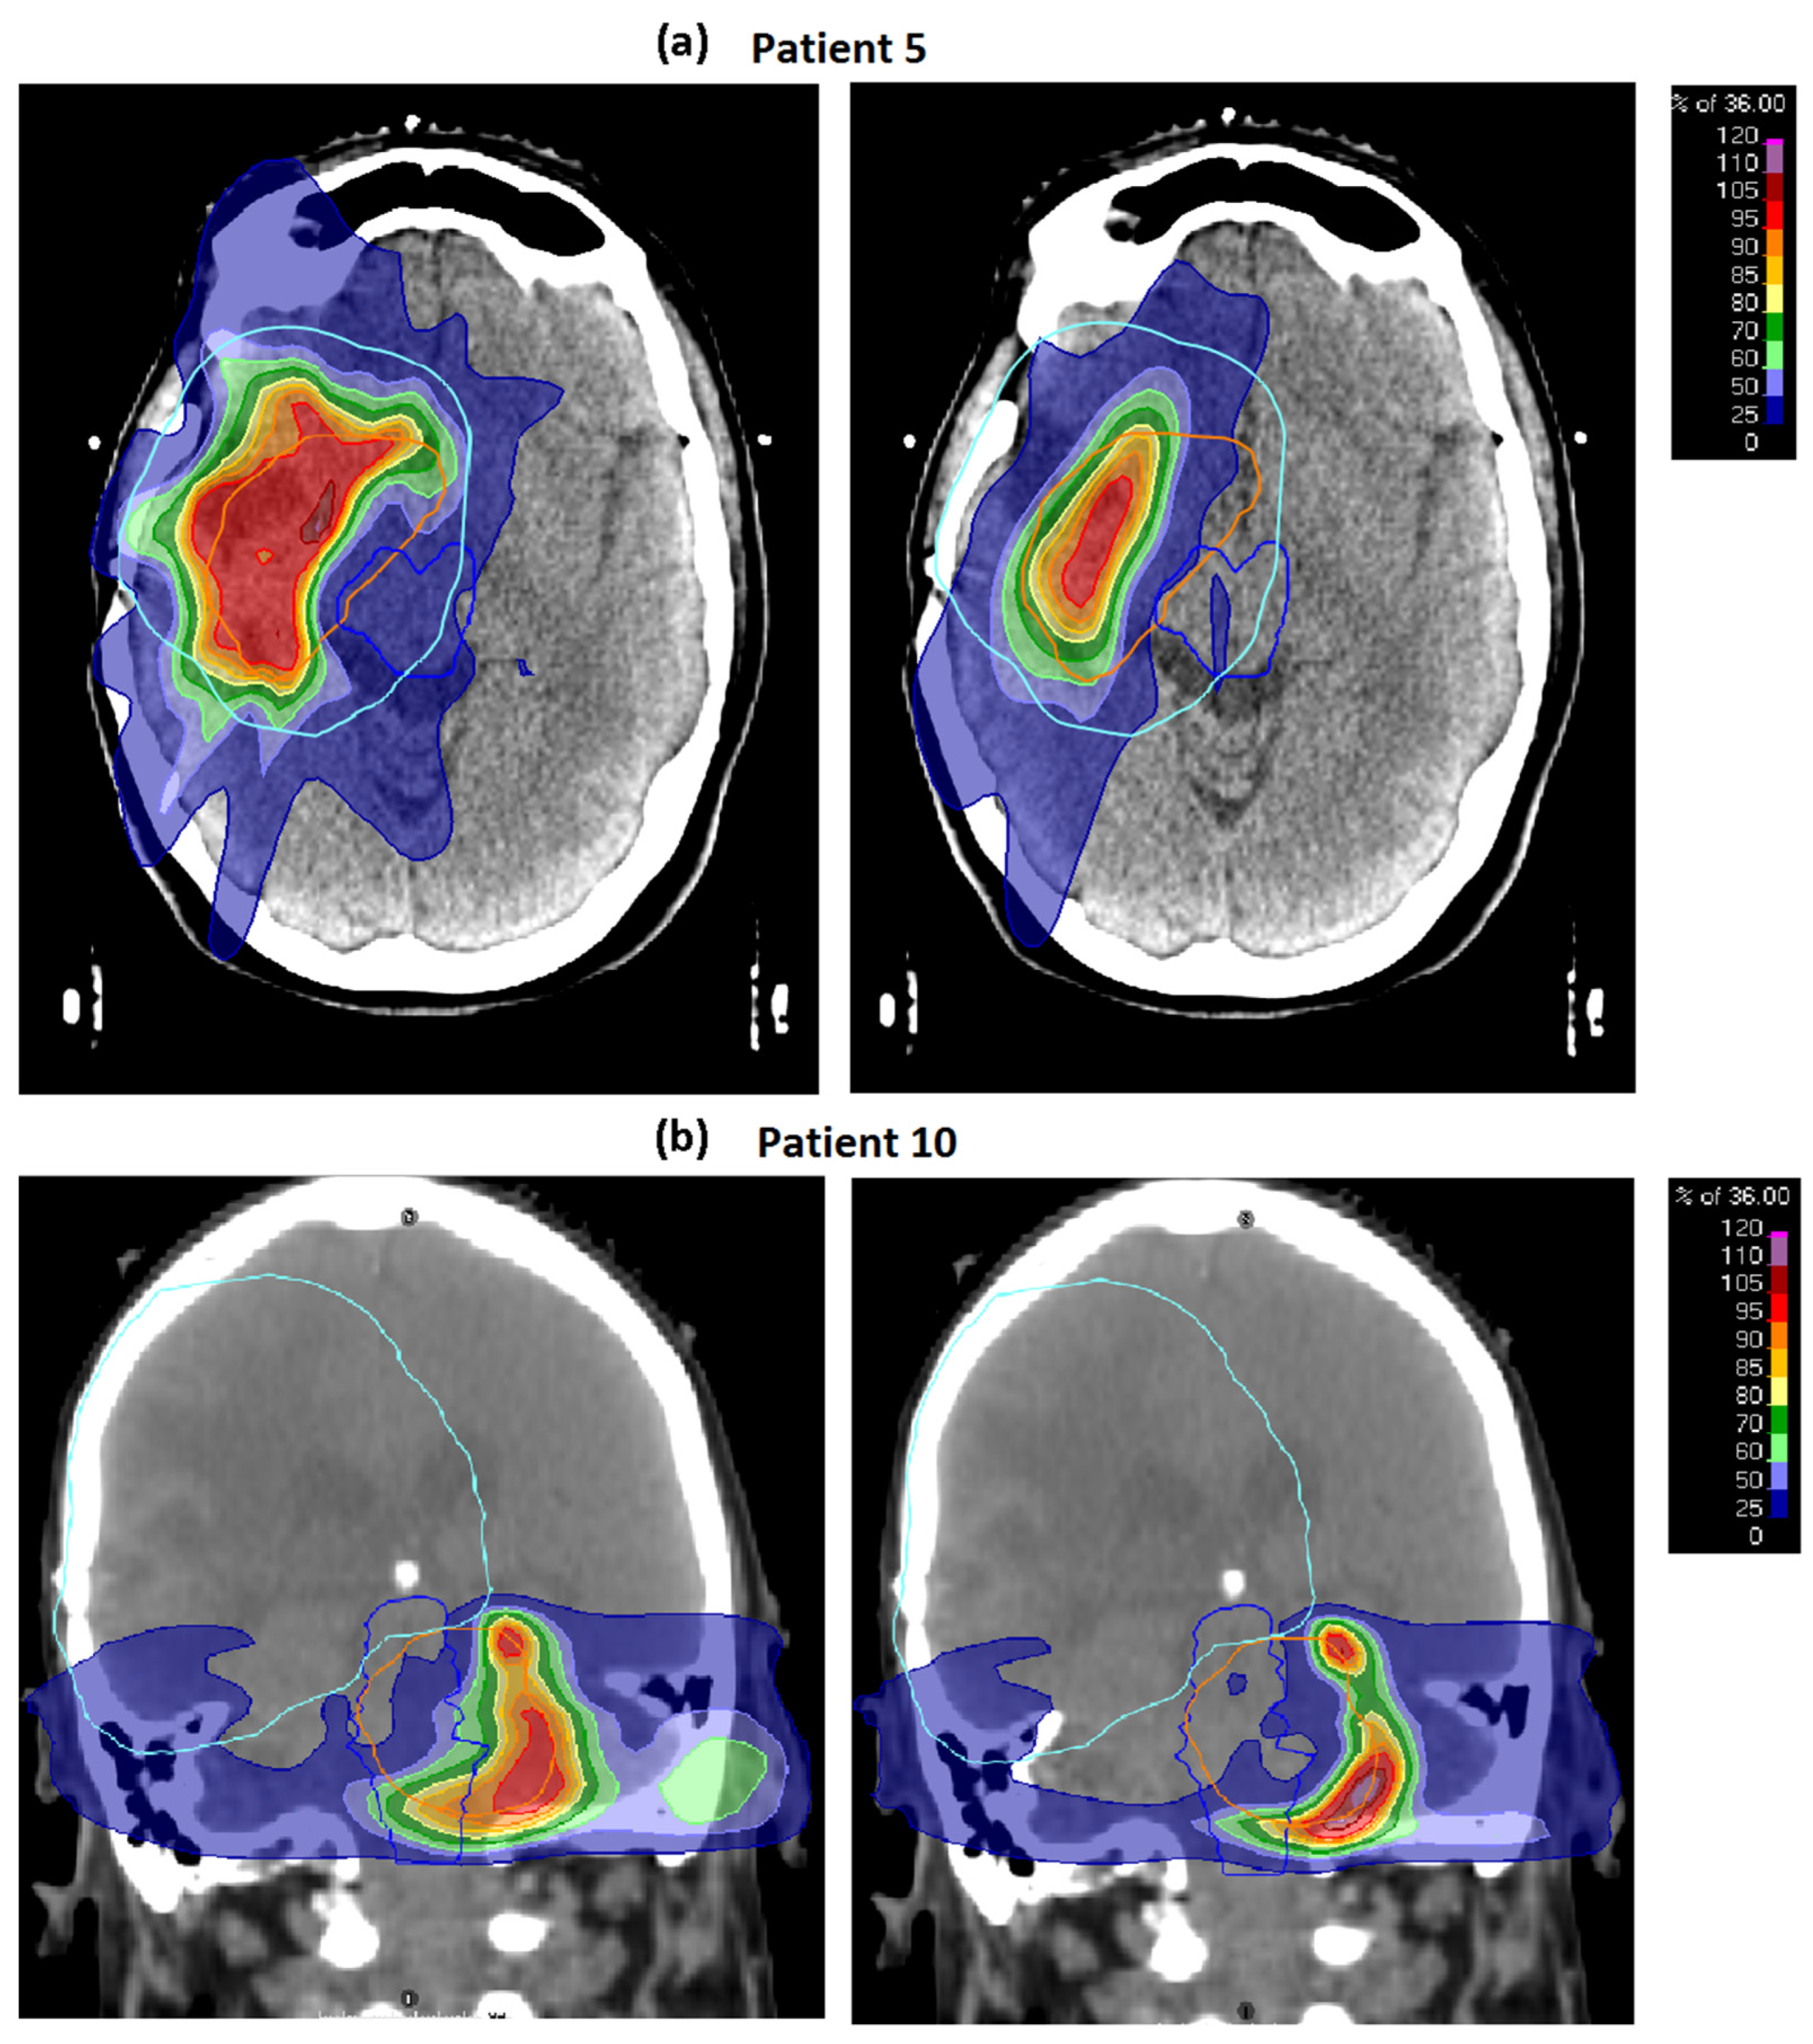

3.1. Baseline Plans

3.2. Robustness

3.2.1. Geometric Robustness